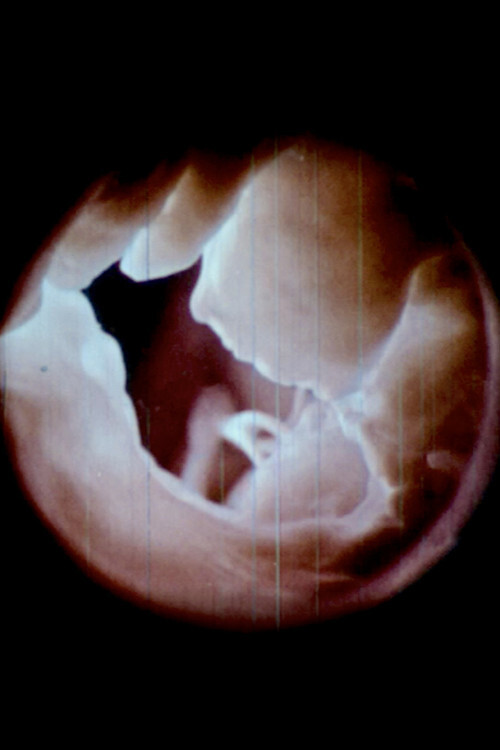

心 Heart (Radical 61) (2020)

心 Heart (Radical 61)

• Эрин Espelie

• Время: 21 мин.